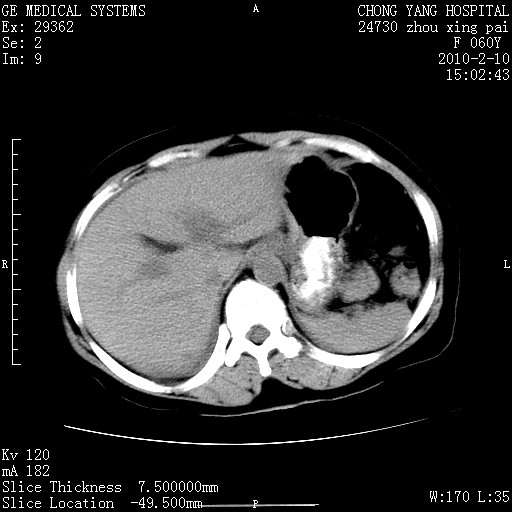

标题: CT24682:F60Y 腹痛 其它不详 [打印本页]

标题: CT24682:F60Y 腹痛 其它不详

胆总管末端梗阻!结石?胰腺影增粗,以胰腺头部为著,胰周看见渗出影,双侧胸腔积液,(胸膜反应)考虑胰腺炎。

1)胆总管末端梗阻,不排除结石所致可能。2)胰腺炎。3)慢性胆囊炎可能。4)左侧输尿管上段扩张。5)少量腹水。6)双侧少量胸腔积液,伴两下肺部分肺萎陷。

1)胆囊炎。2)胆源性胰腺炎。3)右肾周筋膜增厚,肾旁前间隙积液。4)左侧输尿管上段扩张。5)少量腹水。6)双侧少量胸腔积液,伴两下肺部分肺膨胀不全。

1)胆总管末端梗阻。2)胰腺炎。3)慢性胆囊炎可能。4)左侧输尿管上段扩张。5)少量腹水。6)双侧少量胸腔积液,伴两下肺部分肺萎陷。